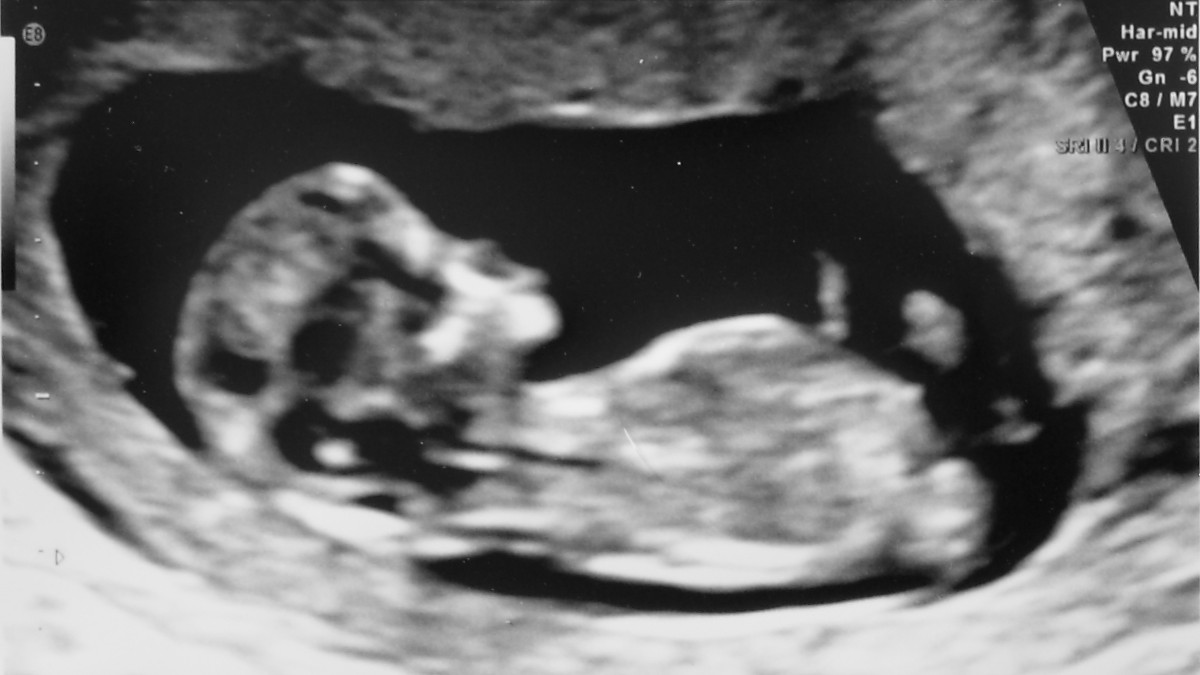

Il 21 marzo il mondo celebra la "giornata della Sindrome di Down". Ma tutti gli altri giorni si "libera" dei bambini Down con test prenatali e aborto selettivo

Il 21 marzo è la giornata mondiale della Sindrome di Down. 21, come la trisomia che avremmo riscontrato in 27 bambini europei ogni 10 mila nati, invece sono stati solo 10. Senza aborti selettivi ne sarebbero nati 17 mila, ne sono nati invece 8 mila. È quanto conclude uno studio pubblicato a dicembre dall’European Journal of Human Genetics che ha calcolato quanti bambini Down sono nati tra il 2011 e il 2015 e quanti ne sarebbero nati se non fossero stati abortiti proprio perché “Down”, cioè individuati come tali dagli screening prenatali.

Rispetto alle stime previste, in Spagna sono nati l’83 per cento di questi bambini in meno, in Italia il 71 per cento in meno. In Danimarca la riduzione è stata del 79 per cento: nel paese più felice ed egualitario del mondo, nel 2019 sono nati solo 18 bimbi con la trisomia 21. L’Islanda, dove la riduzione 2011-2015 è pari al 69 per cento, è vicina al 100 per cento di popolazione “sana”: non vedono la luce più di due bimbi Down all’anno, nati per errore, cioè non segnalati dagli screening. Nel Regno Unito i nati con Sindrome di Down sono stati il 54 per cento in meno delle attese. Dati in linea con la media europea nel periodo del debutto dei Nipt (Not Invasive Prenatal Test), gli screening delle principali anomalie cromosomiche fetali in gravidanza. Il Regno Unito è un caso emblematico: qui, dove nove donne su dieci che ricevono diagnosi di Sindrome di Down decidono di abortire, Heidi Crowter, attivista 25enne con la trisomia 21, è riuscita a fare accogliere all’Alta Corte la richiesta di riesame giudiziario della normativa che autorizza la soppressione di disabili come lei fino alla nascita.

In Francia, alla fine del periodo considerato dallo studio mancavano all’appello il 68 per cento delle nascite attese di bambini con la Sindrome di Down: qui a giugno è stata respinta per un pugno di voti una misura che avrebbe aperto all’individuazione in provetta anche della trisomia 21. Eppure, complice il crescere dell’età media delle donne in gravidanza, dati Eurocat attestano che negli ultimi 35 anni la frequenza con cui si verificano i concepimenti di bambini con la Sindrome di Down è quasi raddoppiata: da uno ogni 735 negli anni Ottanta a uno ogni 400 oggi (e tra il 2016 e il 2018 sono 39 i bambini nati vivi ogni cento concepiti con trisomia 21). Puntare a estirpare una sindrome eliminando il malato, insomma, è un sogno eugenetico a cui curiosamente oppongono resistenza i concepiti.

Lo scopo della diagnosi prenatale non andrebbe mai messo in discussione: grazie agli screening è possibile capire come prendersi cura di un bambino, individuare condizioni che potrebbero causare problemi di salute man mano che il feto cresce, preparare la donna e permettere a chi non si sente all’altezza della sfida di crescere un bimbo con la trisomia 21 di poterlo dare in adozione: quando abbiamo iniziato a promuoverli per selezionare i figli, usando l’aborto come mezzo per il “controllo di qualità” della popolazione europea? Nell’epoca di tutti i diritti umani, delle vite che tutte valgono, quelle dei bambini con la Sindrome di Down sono uguali alle altre solo il 21 marzo.